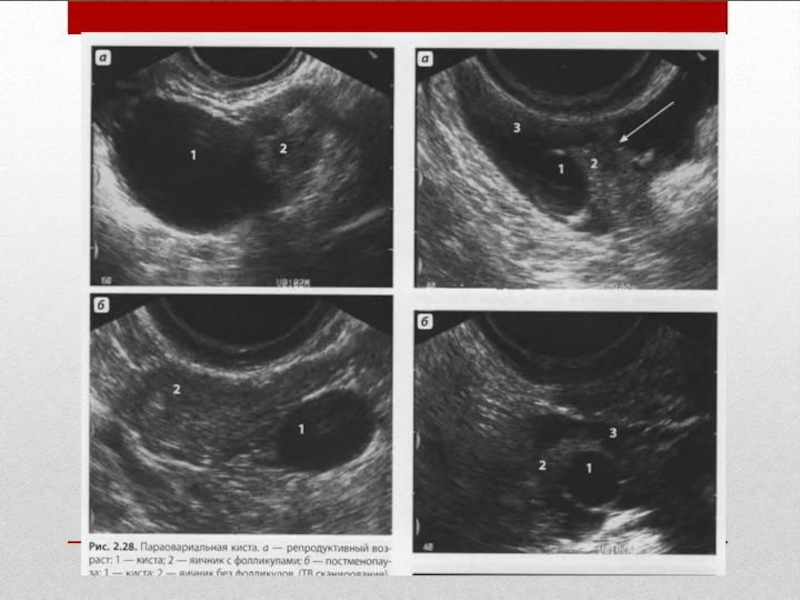

Слайд 12Основным и практическим единственным УЗ признаком параовариальных кист является визуализация

отдельно расположенного яичника.

Киста круглая или овальная, однокамерная. Её стенка

тонкая (около 1мм). Содержимое кист в основном анэхогенное, однородное. Иногда встречается пристеночный компонент губчатой структуры.

В параовариальных кистах может определяться мелкодисперсная взвесь, смещаемая при перкуссии

При ЦДК – аваскулярны. При динамическом наблюдении не подвергаются регрессии.